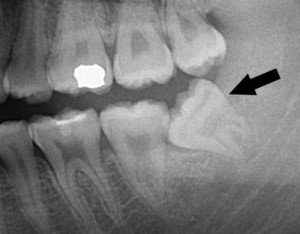

Răng khôn mọc lệch sẽ có nguy cơ gây sưng lợi, viêm nướu, việc vệ sinh răng miệng khó sẽ là cơ hội cho vi khuẩn xâm hại. Vì vậy, không nên xem thường việc mọc răng khôn, phải theo dõi và điều trị để tránh làm ảnh hưởng đến các răng bên cạnh.